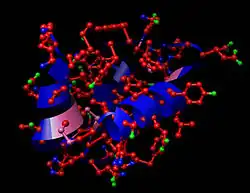

L'insuline est l'une des 20 protéines humaines connues pour pouvoir former des fibres amyloïdes in vitro. La formation de ces fibres est principalement liée au pH, à la température et à la surface des matériaux auxquels l'insuline est exposée[35].

Bien que l'agrégation amyloïde de l'insuline n'ait jamais été observée in vivo chez l'humain, des dépôts localisés de fibres amyloïdes d'insuline ont été observés près du site d'injection chez des patients diabétiques[36]. La formulation de l'insuline thérapeutique permet de réduire son agrégation.